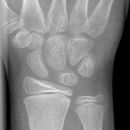

distale Radiusfraktur